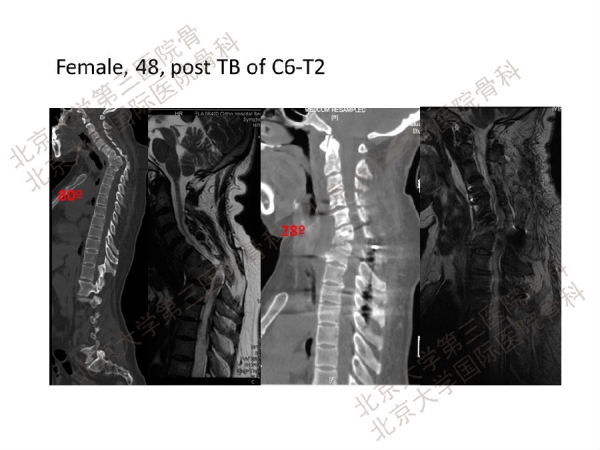

如今,脊柱截骨术因其可以取得很好的矫正效果,临床应用越来越广泛。但是,脊柱截骨手术并风险大、并发症高,脊柱外科医生应予以高度重视,在临床上必须严格掌握适应证。脊柱截骨矫形手术容易出现硬膜破损、神经根损伤、脊髓损伤、胸膜损伤等等并发症。其中,术中及术后早期出现的神经并发症更是不容忽视。

陈仲强教授指出,这可能与截骨过程手术操作的震动、手术操作对脊髓的直接损伤、矫正畸形时截骨断端错动、矫形导致脊髓过度短缩或拉伸、脊髓血供减弱或障碍、内置物或植骨块移位压迫脊髓、术后伤口深部血肿压迫脊髓,以及其他不明原因有关。